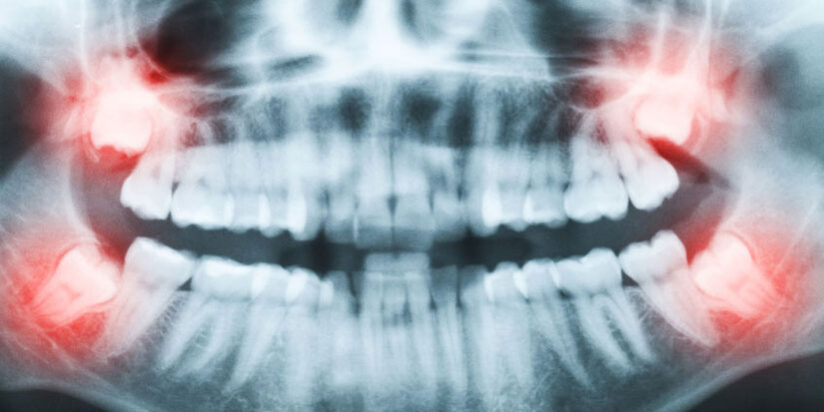

As with any surgical procedure, your surgeon will want to initially conduct a thorough examination of the wisdom and surrounding teeth. Panoramic or digital x-rays will be taken in order for your surgeon to evaluate the position of the wisdom teeth and determine if a current problem exists, or the likelihood of any potential future problems. The x-rays can also expose additional risk factors, such as deterioration or decay of nearby teeth. Early evaluation and treatment (typically in the mid-teen years) is recommended in order to identify potential problems and to improve the results for patients requiring wisdom teeth extractions. Only after a thorough examination can your surgeon provide you with the best options for your particular case.